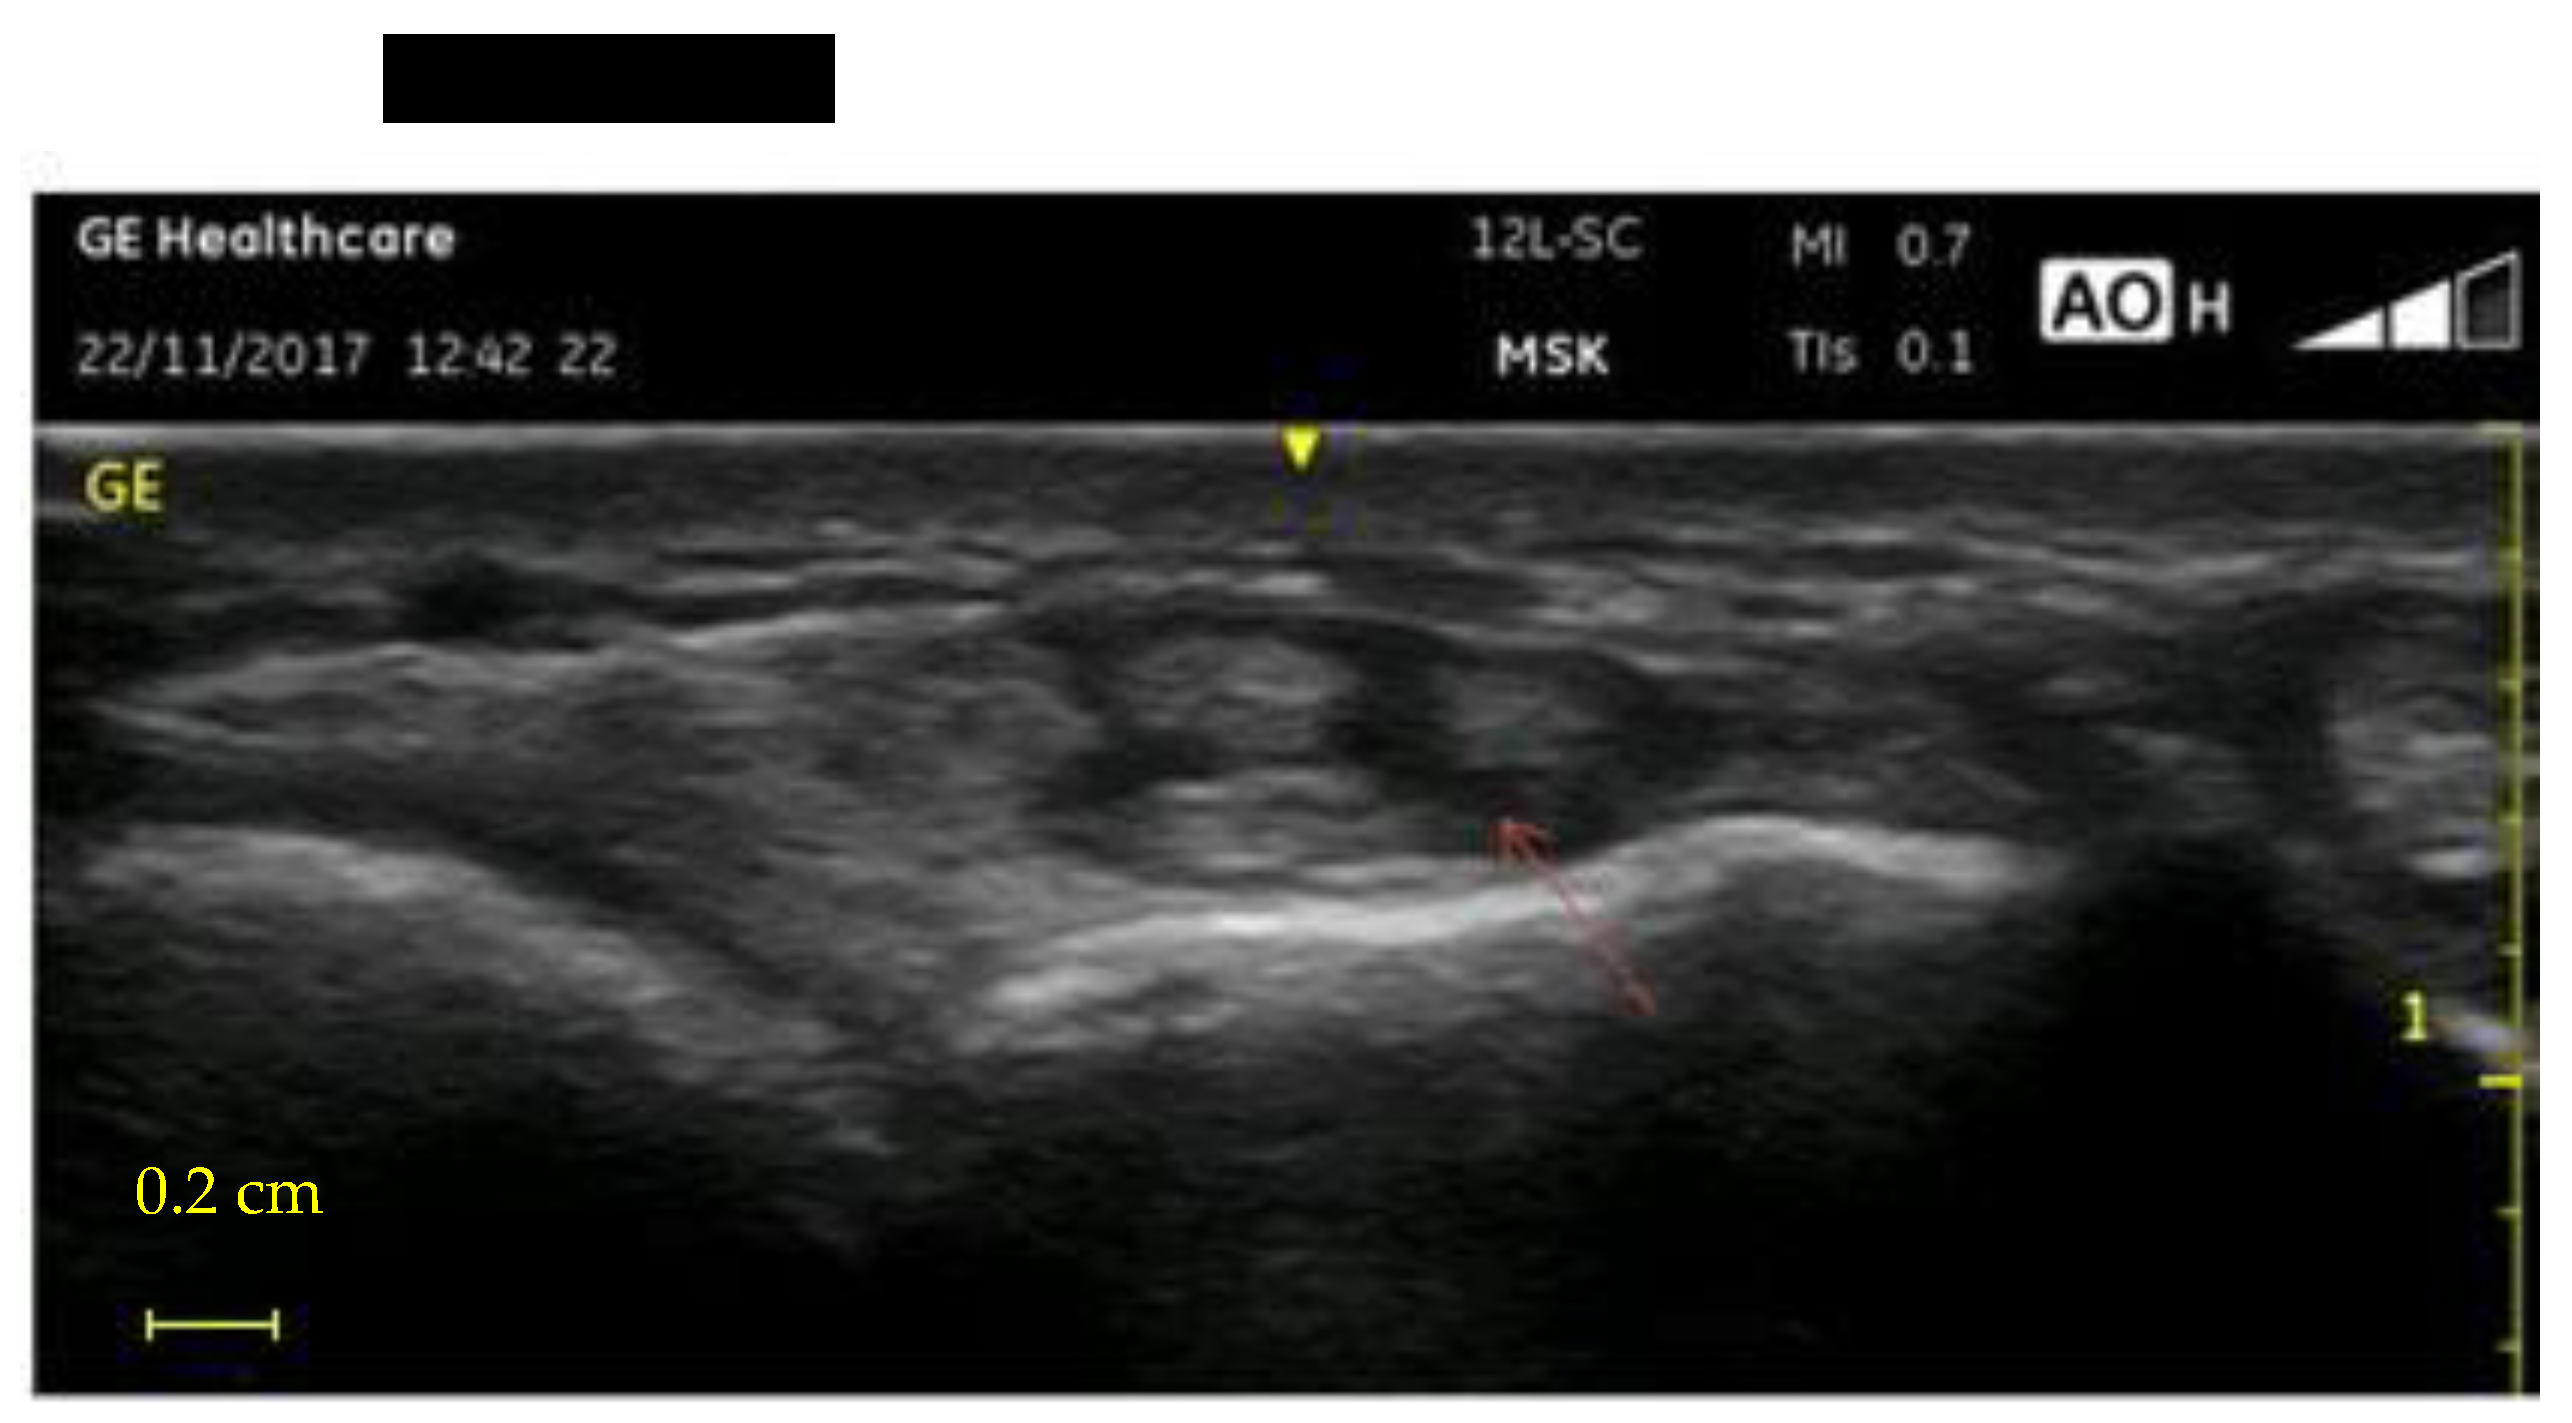

- UI of the hand-wrist area, performed with portable ultrasound device (Venue Scan, Venue 40, GE Healthcare®, Chicago, IL, USA) that allowed the researchers to store the examinations for further evaluation and discussion with other hospital experts in the final evaluation of all cases. A trained sonographer performed the wrist ultrasound. According to the European Society of Musculoskeletal Radiology’s protocol (ESSR) [23], acoustic windows were investigated in both the dorsal wrist, focusing on the extensor tendons and the radiocarpal joint, and the ventral wrist, focusing on the flexor tendons and the median nerve (Table 1).

| US cross-sectional area >0.10 cm2 | |||

| Dominant hand | 12 (32%) | 31 (81.5%) | p < 0.001 |

| Non-dominant hand | 10 (25%) | 21 (55.2%) | p = 0.008 |